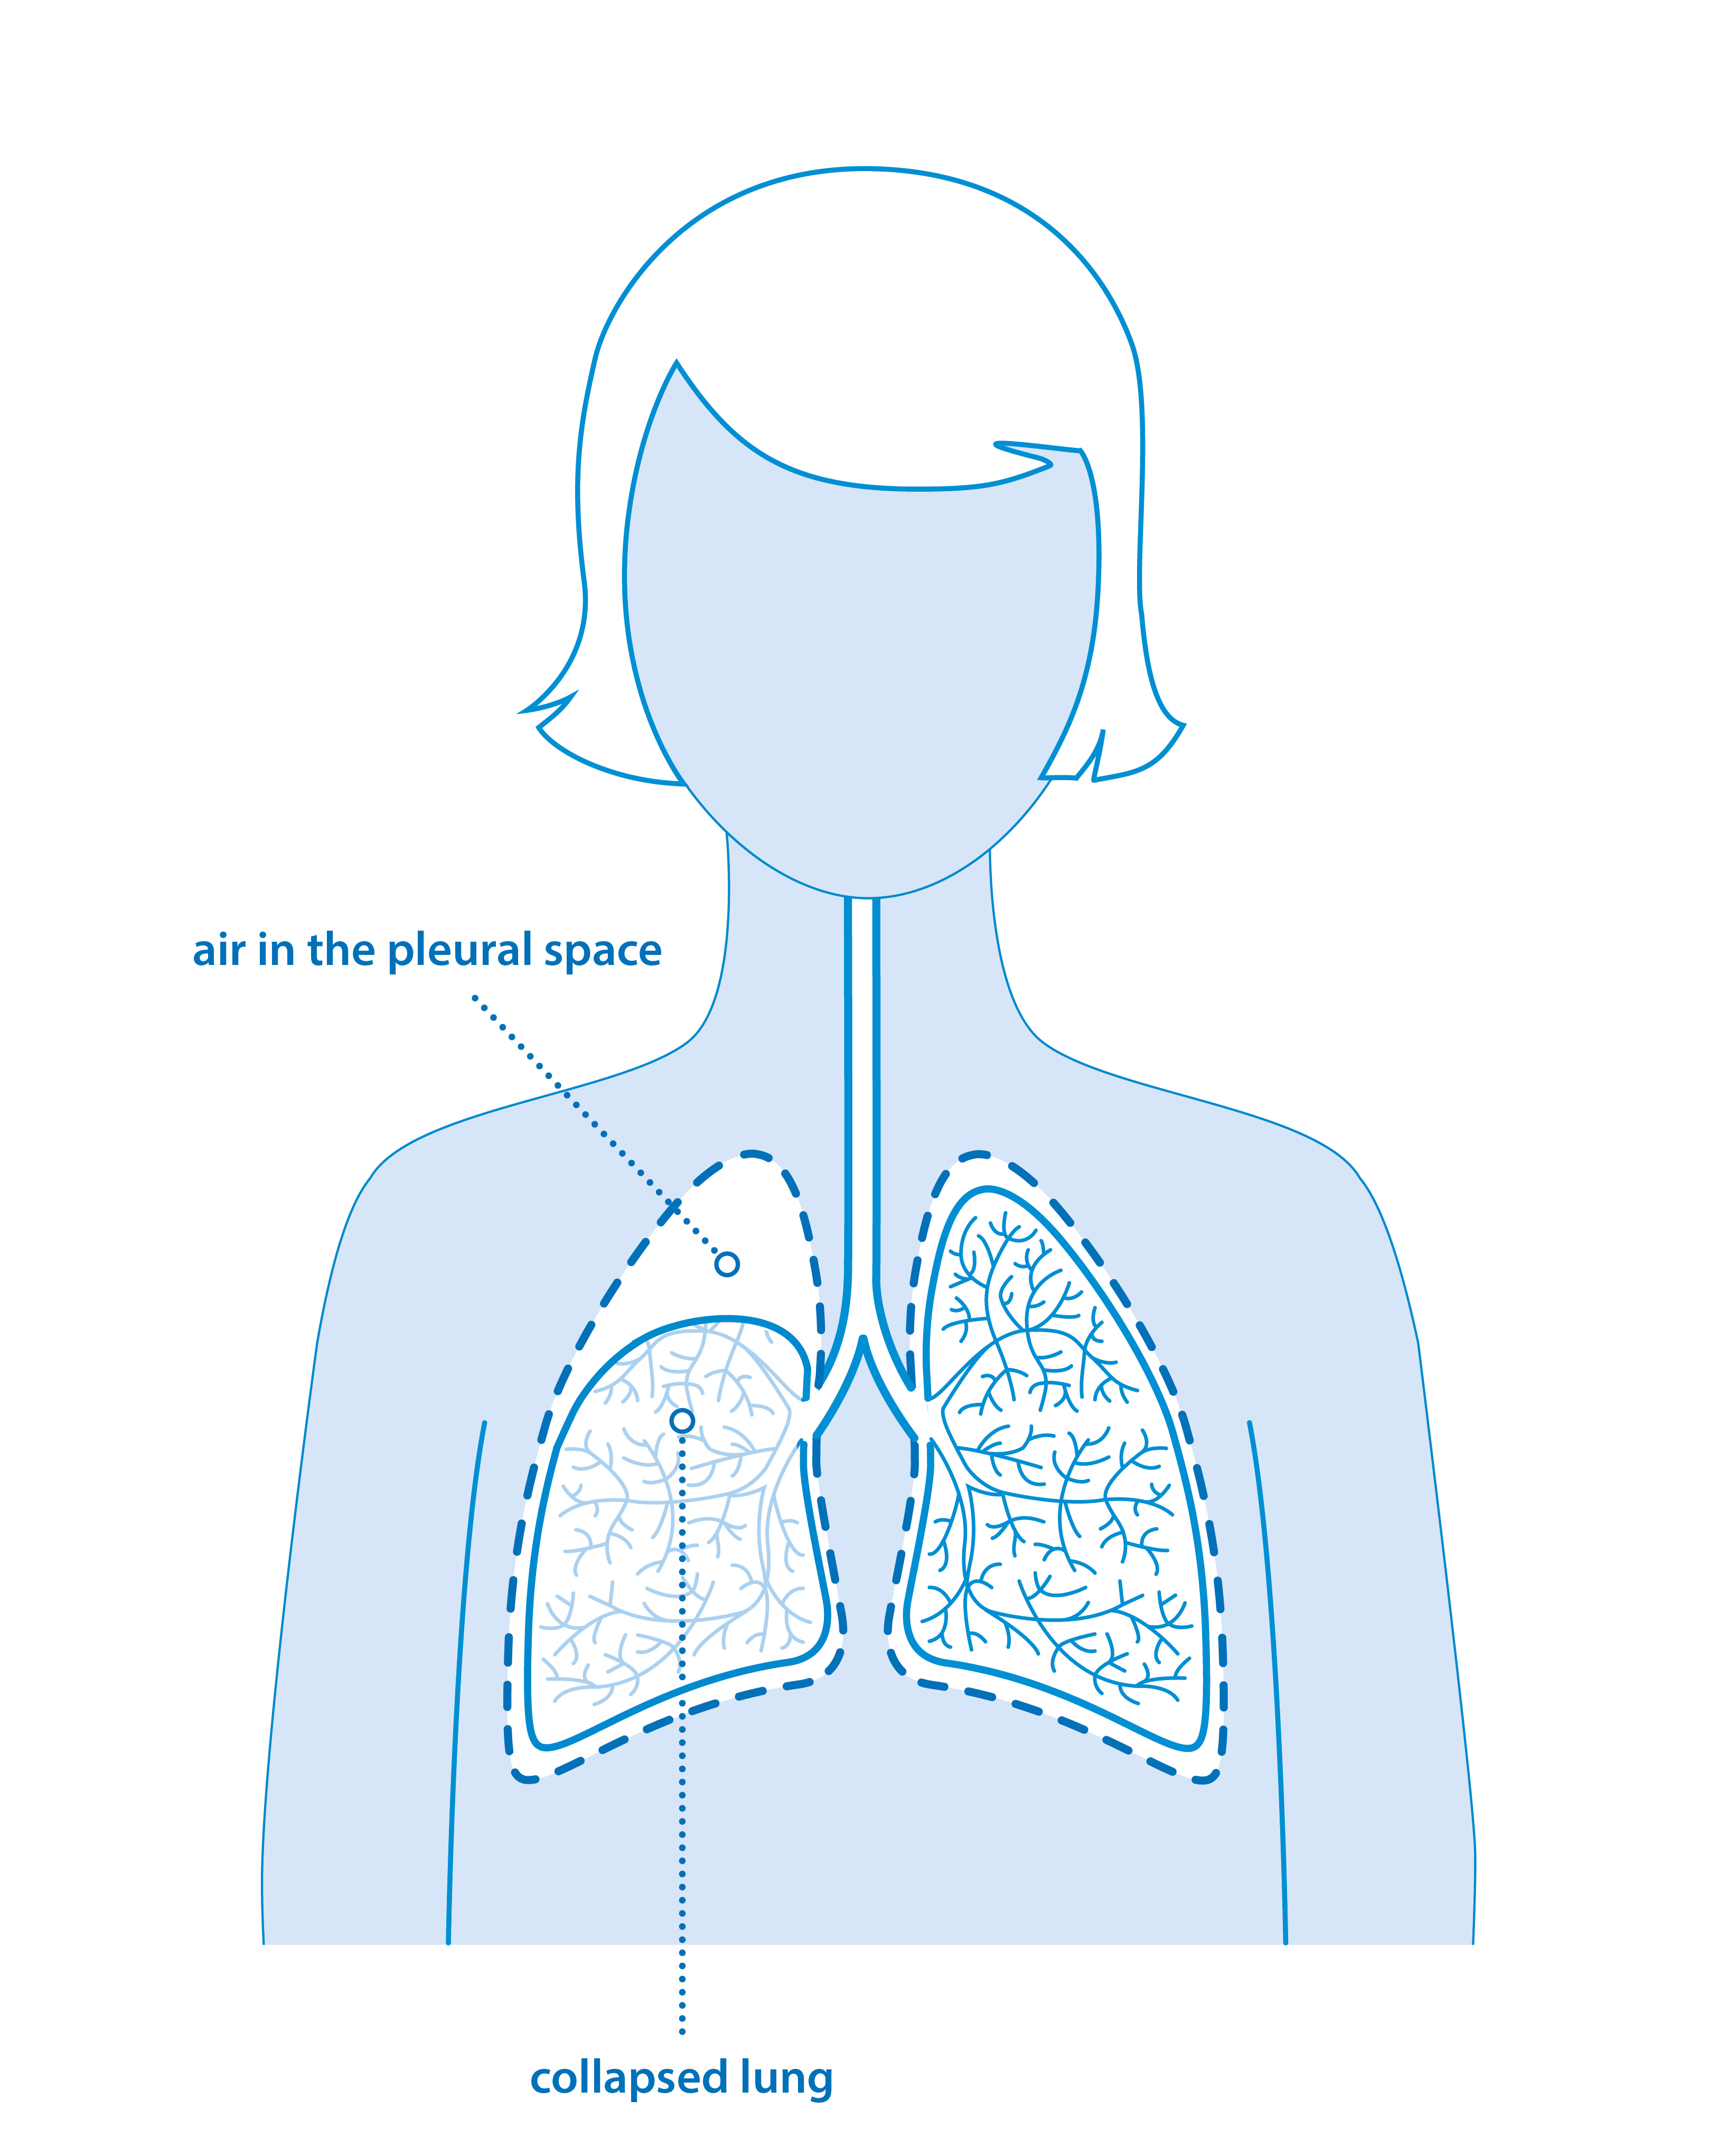

Схемы дыхания: Пневмоторакс на изображениях